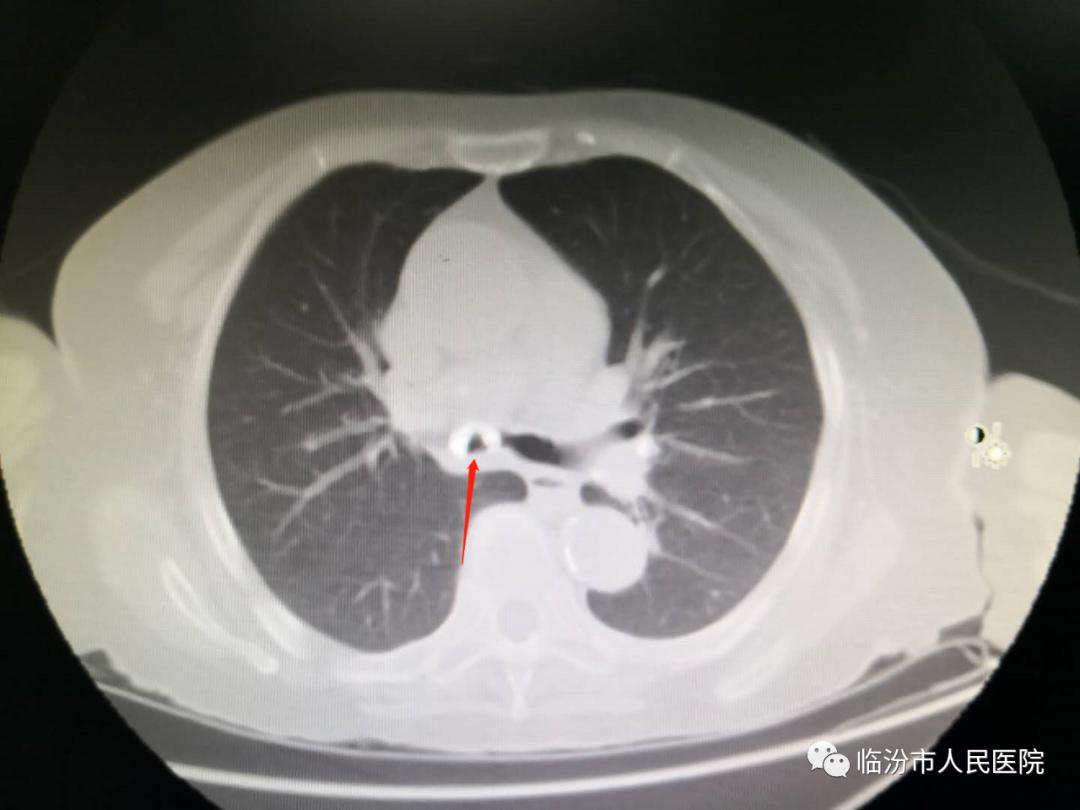

ct检查后提示右主支气管内异物

胸部ct:主气管针形金属异物,针尖已经扎入主气管右侧壁

都是气管内异物惹的祸